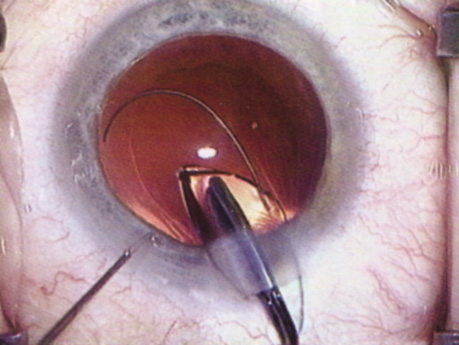

| There are many different approaches to disassembling the lens nucleus; each

level of experience. Slow-Motion Phacoemulsification Slow-motion phacoemulsification is a technique that seeks to maintain a stable anterior chamber during phacoemulsification while minimizing the volume of fluid that flows through the eye. By minimizing fluid inflow, there should be less endothelial cell loss and, therefore, less early postoperative corneal edema. Additionally, low inflow levels decrease the chance of forcing fluid through any areas of weakened zonules, which could create fluid lacunae within the vitreous gel, leading to positive pressure and possible vitreous prolapse. Chamber collapses are less likely because vacuum levels and aspiration rates are low; therefore, the risk of iris damage or posterior capsule rupture should be diminished. Because the technique involves low vacuum, aspiration, and inflow, it may be difficult to hold onto nuclear fragments for some methods of chopping the nucleus. Divide Techniques Divide techniques attempt to emulsify the nucleus by separating it into two or four pieces. Grooves carved into the nucleus facilitate separation of the pieces. The grooves can be achieved using low vacuum levels because complete occlusion of the phacoemulsification tip during is neither needed nor desired at this stage of the procedure. If one makes the groove at least twice the diameter of the phacoemulsification tip, there is better visualization of the walls of the groove, and thus better understanding of the groove's depth. A wide groove also results in the surgeon debulking more of the nucleus in the capsular bag, so that when the pieces are brought forward, less emulsification needs to be performed anteriorly. While fashioning the groove, it is important not to move the phacoemulsification tip faster than it is emulsifying. Advancing the tip too quickly causes the entire nucleus to move with the tip and may lead to subincisional zonular damage. The groove depth required to allow cracking depends on the density of the central and posterior nucleus. A hard nucleus with a dense posterior plate may not crack even if grooved through 90% of its thickness. Likewise, a fetal nuclear cataract may be cracked easily after grooving only halfway through. Regardless of the depth of the groove, the surgeon should place the cracking instruments at the most posterior aspect of the groove before dividing. (Fig. 17). Doing so minimizes stress on the anterior capsulorrhexis and generates forces more likely to result in a successful divide. After the nucleus has been bisected, the surgeon can debulk and emulsify each heminucleus separately. Alternatively, the surgeon can rotate the nucleus 90 degrees and further divide it into quarters in a similar fashion. After the surgeon has completed the divide portion of the procedure, vacuum and aspiration levels can be increased. By increasing vacuum and aspiration levels, the surgeon will find it easier to bring nuclear pieces to the phacoemulsification port. Additionally, higher vacuum levels hold the nuclear segments more tightly to the phacoemulsification port, resulting in more efficient phacoemulsification and better control. ”Chop” Techniques In 1993, Kunihiro Nagahara introduced a method of chopping the nucleus into pie slice–shaped wedges for emulsification (Fig. 18). Chopping techniques can be defined as vertical or horizontal chopping. Both chopping techniques involve burying the phacoemulsification tip into the center of the nucleus, holding it in place with increased vacuum. When performing a vertical chop, the chopping instrument is inserted through a second incision and placed beneath the anterior capsular rim. The chopper is directed peripherally, and then drawn posteriorly and centrally toward the phacoemulsification tip, causing the nucleus to crack. The horizontal chop differs in that the chopper does not need to be placed under the anterior capsular rim and the chop does not begin at the lens periphery. Instead, the chopping instrument is placed in the nucleus near the anterior capsulorrhexis edge and then directed posteriorly until it meets the buried phaco tip. Both chopping techniques take advantage of the natural cleavage planes between the nuclear lens fibers, similar to chopping a piece of wood with an ax. Each wedge can be brought centrally using a second instrument or the vacuum of the phacoemulsification tip for emulsification away from the posterior capsule, iris, capsulorrhexis edge, and bag periphery. Then the nucleus is rotated and similar maneuvers are performed with each segment until the entire nucleus has been emulsified. Smaller, more manageable wedges can be chopped off the nucleus for dense nuclei and larger pieces sectioned from softer nuclei.